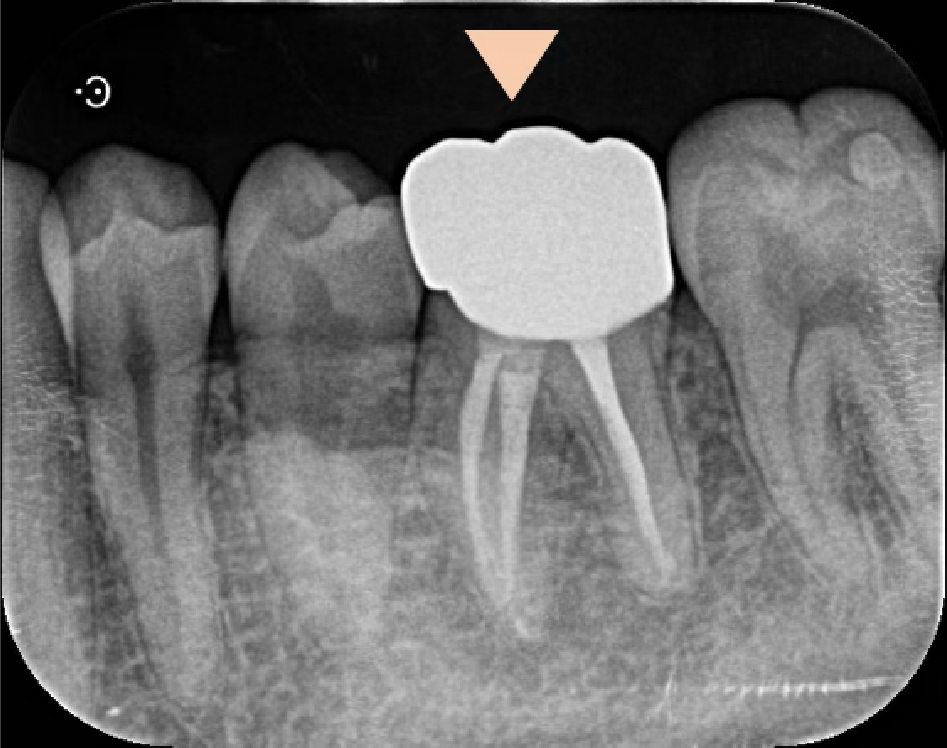

左下6番(第一大臼歯)のレントゲンを撮影したところ、根の先には透過像(黒い影)が認められ、根管内には白く移る貼薬材料(消毒の薬:水酸化カルシウム製剤)と思われる材料が詰められている状態でした。

このような場合、痛みの原因は根の先の膿(根尖性歯周炎)ではなく、繰り返し治療を続けることにより歯そのものの痛みの閾値が低下し、感覚過敏のような状態になっていることによるものと推測されます。

歯冠側にはレジンによる詰め物が認められますが、う蝕の残存も疑われる状態でした。う蝕(虫歯)が残っている状態でいくら根の中を清掃していても、根管内への持続的な細菌感染が持続してしまい、痛みが続く原因のひとつとなります。

術後6ヶ月時点で、症状はかなり軽減しました。レントゲン的には根の先の黒い影は消失しています。

元々根の先にわずかに存在していた透過像(黒い影)は消失し、症状が軽減後、セラミッククラウンを装着し治療は完了しました。